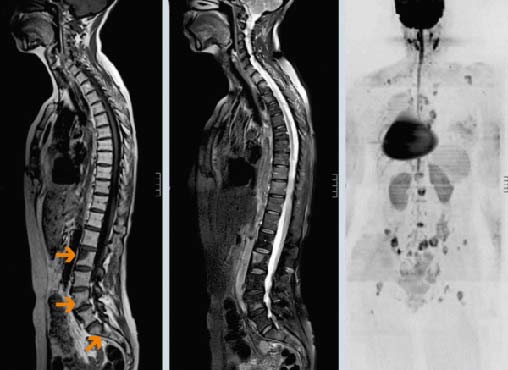

При опухолях позвоночника массаж запрещен